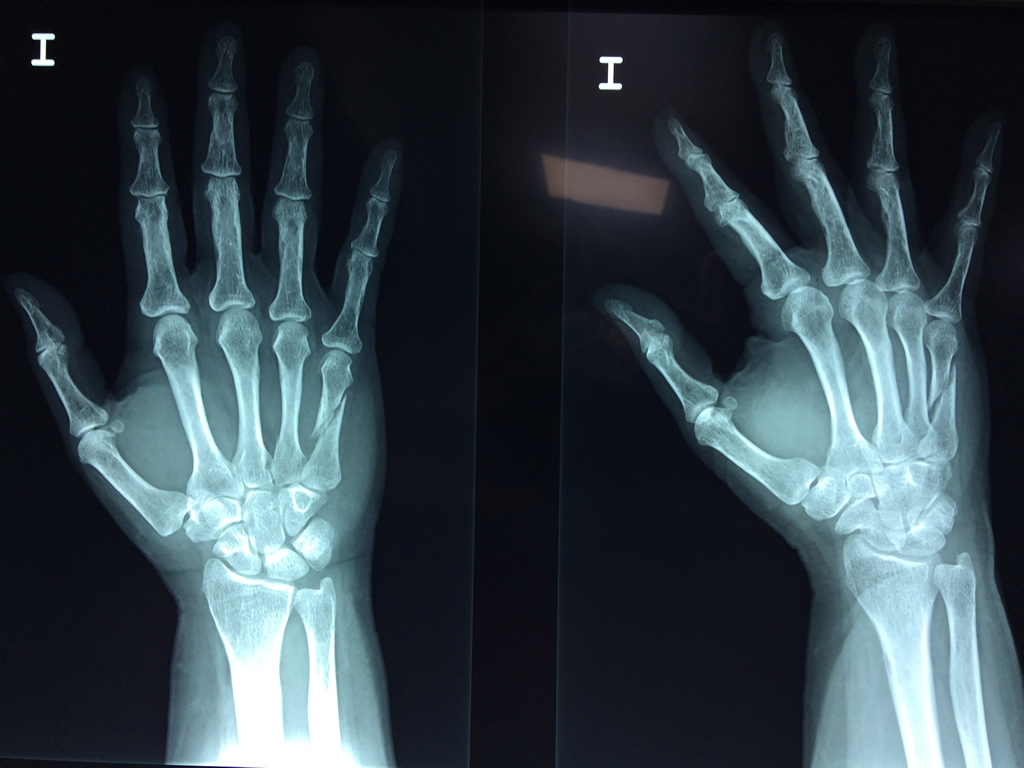

Cirugías de Codos - Cirugías de Muñecas y Manos

Los procedimientos más comunes en cirugía de la mano son aquellos destinados a reparar traumatismos, incluyendo lesiones de tendones, nervios, vasos sanguíneos, y articulaciones; huesos fracturados; y quemaduras, cortes, y otros daños de la piel.